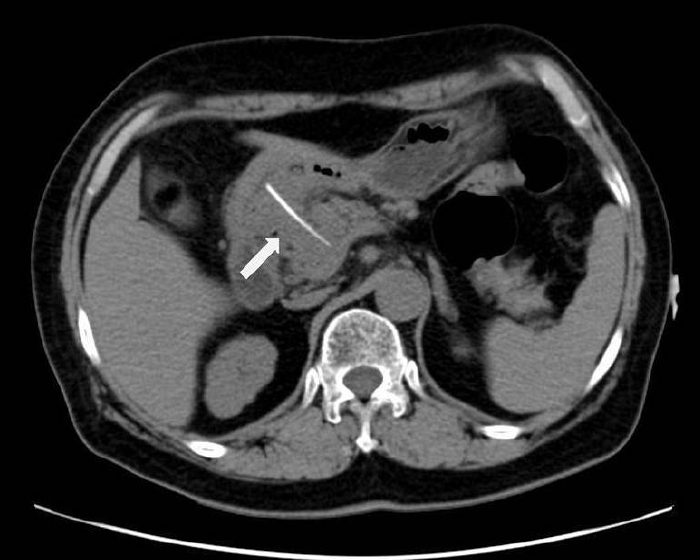

Figure 1.

In the first case, a computed tomography scan showed a linear calcified body that appeared to penetrate the antrum of the stomach into the pancreatic neck.